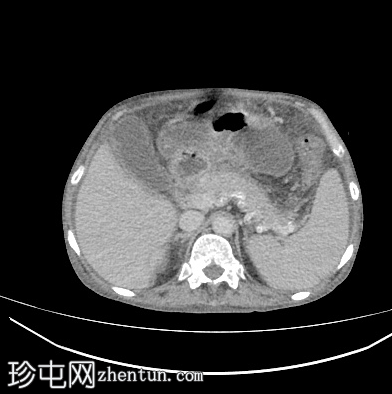

轴位增强扫描

门静脉期

肝脏轻度肿大,未见肝内胆管扩张。近端和中段胆总管扩张至8 mm,远端突然中断,门周脂肪间隙增厚。

胰腺轻度肿大,胰周脂肪间隙增厚,符合急性胰腺炎表现。

胃大弯壁内可见一囊肿,大小为7.6 × 4.3 cm,囊壁厚度为2.5 mm,可见强化。脾门处可见另一囊肿,大小为 4.8 × 3.0 cm。

盲肠和升结肠壁水肿增厚,可能为反应性改变。

腹主动脉、脾动脉、腹腔干和肠系膜上动脉可见动脉粥样硬化改变。

中度腹水。双侧轻度胸腔积液(右侧较左侧多)。